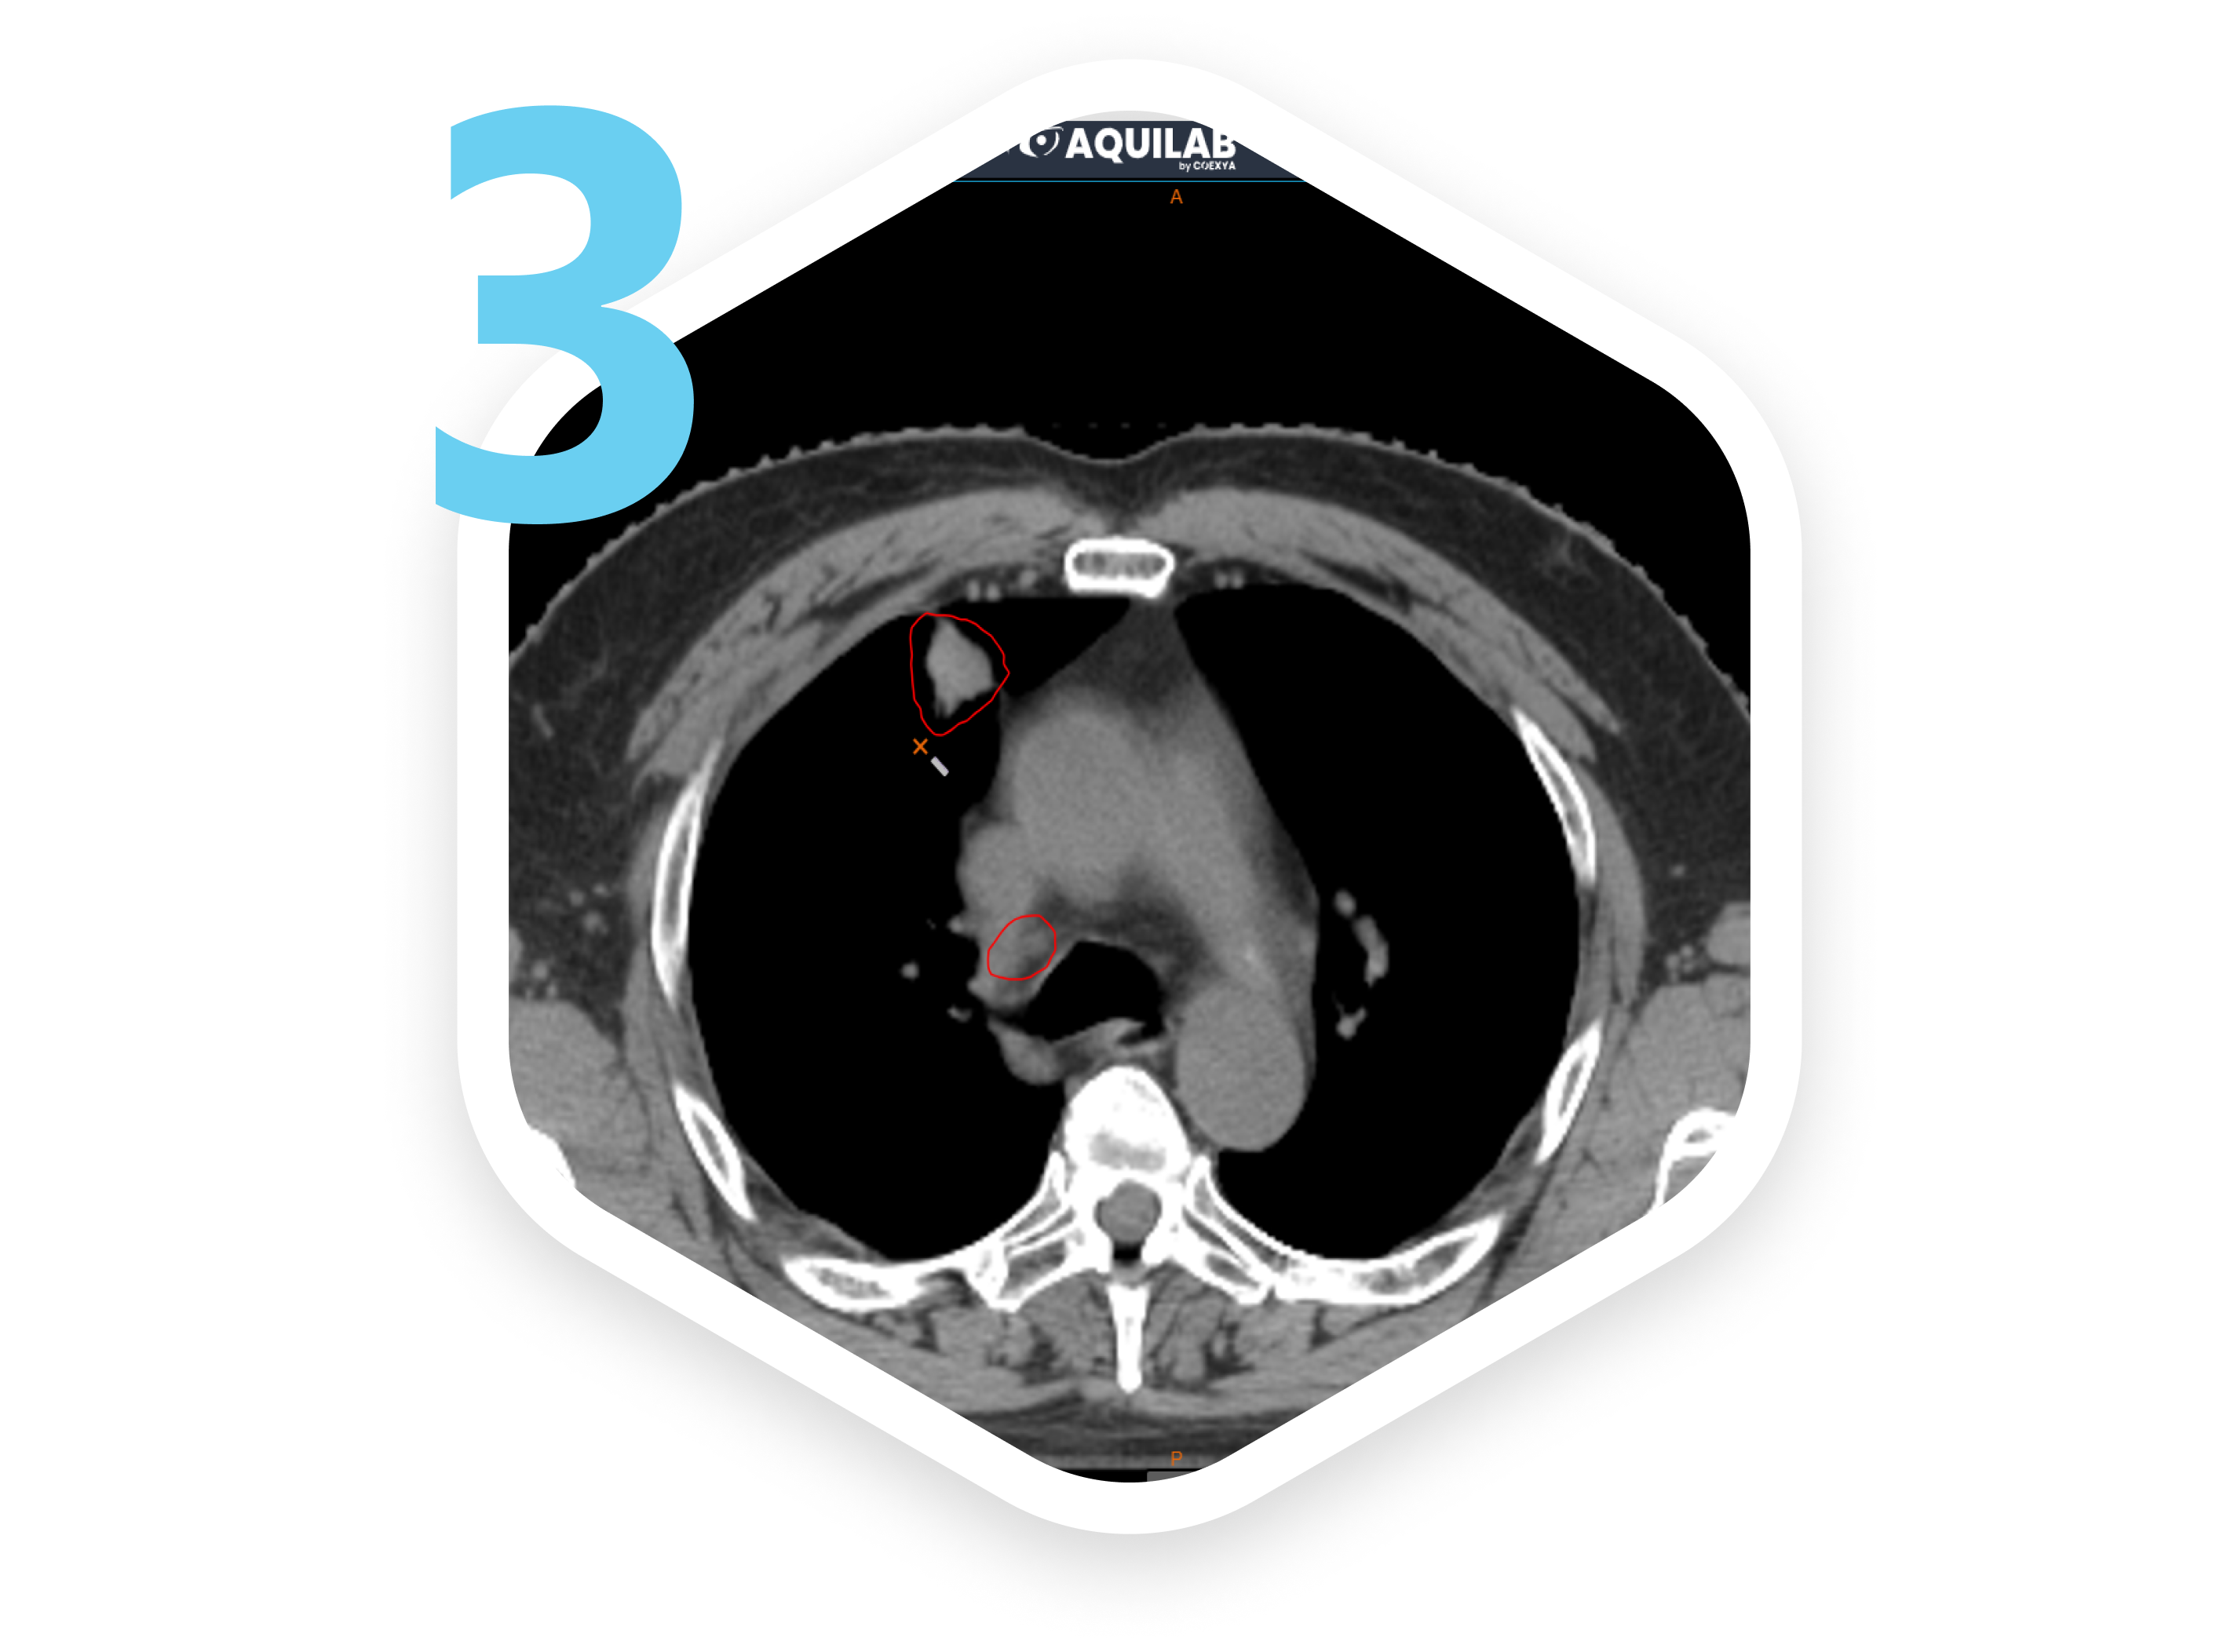

Dans le cadre du "Home Contouring", des cas cliniques sont préparés par AQUILAB, puis mis à disposition sur la plateforme Onco Place Education. Les participants peuvent télécharger les données DICOM et les instructions de délimitation, utilisant leur propre console ou notre web viewer ARTWEB. Les contours sont collectés par notre ingénieur d'application, puis les résultats sont présentés lors de l'événement avec le logiciel d'AQUILAB.

Pour les ateliers "Live Contouring", les cas cliniques sont préparés et disponibles sur la plateforme Onco Place Education. Les participants utilisent ARTWEB en direct pour délimiter le cas, sans nécessité d'installation. Les résultats sont présentés en temps réel avec le logiciel d'AQUILAB.

Le visualiseur web ARTWEB, compatible DICOM et DICOM RT, permet une visualisation et une délimitation en ligne avec une interface configurable. La flexibilité de l'atelier s'adapte aux besoins des organisateurs grâce à une gamme complète de services.